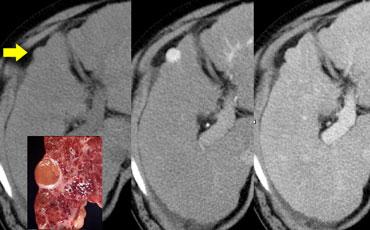

Ung thư biểu mô tế bào gan kích thước nhỏ trên nền gan xơ: không quan sát thấy trên CT không tiêm thuốc (trái), hiện rõ trong thì động mạch (giữa) và không quan sát thấy trong thì tĩnh mạch cửa (phải)

Khả năng phát hiện một tổn thương gan phụ thuộc vào sự chênh lệch tỷ trọng giữa tổn thương và nhu mô gan bình thường.

Trên CT không tiêm thuốc cản quang (NECT), các khối u gan thường không quan sát được do độ tương phản vốn có giữa mô u và nhu mô gan xung quanh quá thấp.

Do đó, cần tiêm thuốc cản quang tĩnh mạch để tăng khả năng hiển thị của các tổn thương.

Khi tiêm thuốc cản quang tĩnh mạch, cần hiểu rằng gan có nguồn cung cấp máu kép.

Nhu mô gan bình thường được cung cấp máu 80% từ tĩnh mạch cửa và chỉ 20% từ động mạch gan, do đó sẽ ngấm thuốc trong thì tĩnh mạch cửa.

Tuy nhiên, tất cả các khối u gan đều nhận 100% nguồn cung cấp máu từ động mạch gan, vì vậy khi ngấm thuốc sẽ xảy ra trong thì động mạch.

Sự khác biệt về nguồn cung cấp máu này dẫn đến các kiểu ngấm thuốc khác nhau giữa khối u gan và nhu mô gan bình thường trong các thì tiêm thuốc cản quang khác nhau (hình).

Trong thì động mạch, các khối u tăng mạch sẽ ngấm thuốc qua động mạch gan khi nhu mô gan bình thường chưa ngấm thuốc, do thuốc cản quang chưa vào hệ thống tĩnh mạch cửa.

Các khối u tăng mạch này sẽ hiện ra là các tổn thương tăng tỷ trọng trên nền gan tương đối giảm tỷ trọng.

Tuy nhiên, khi nhu mô gan xung quanh bắt đầu ngấm thuốc trong thì tĩnh mạch cửa, các tổn thương tăng mạch này có thể bị che khuất.